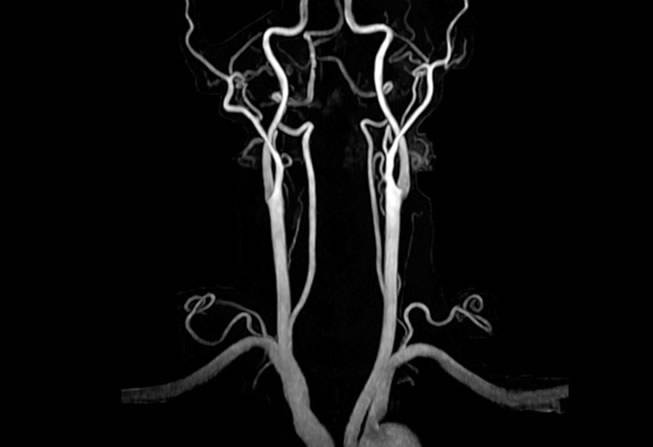

• Angioresonancia